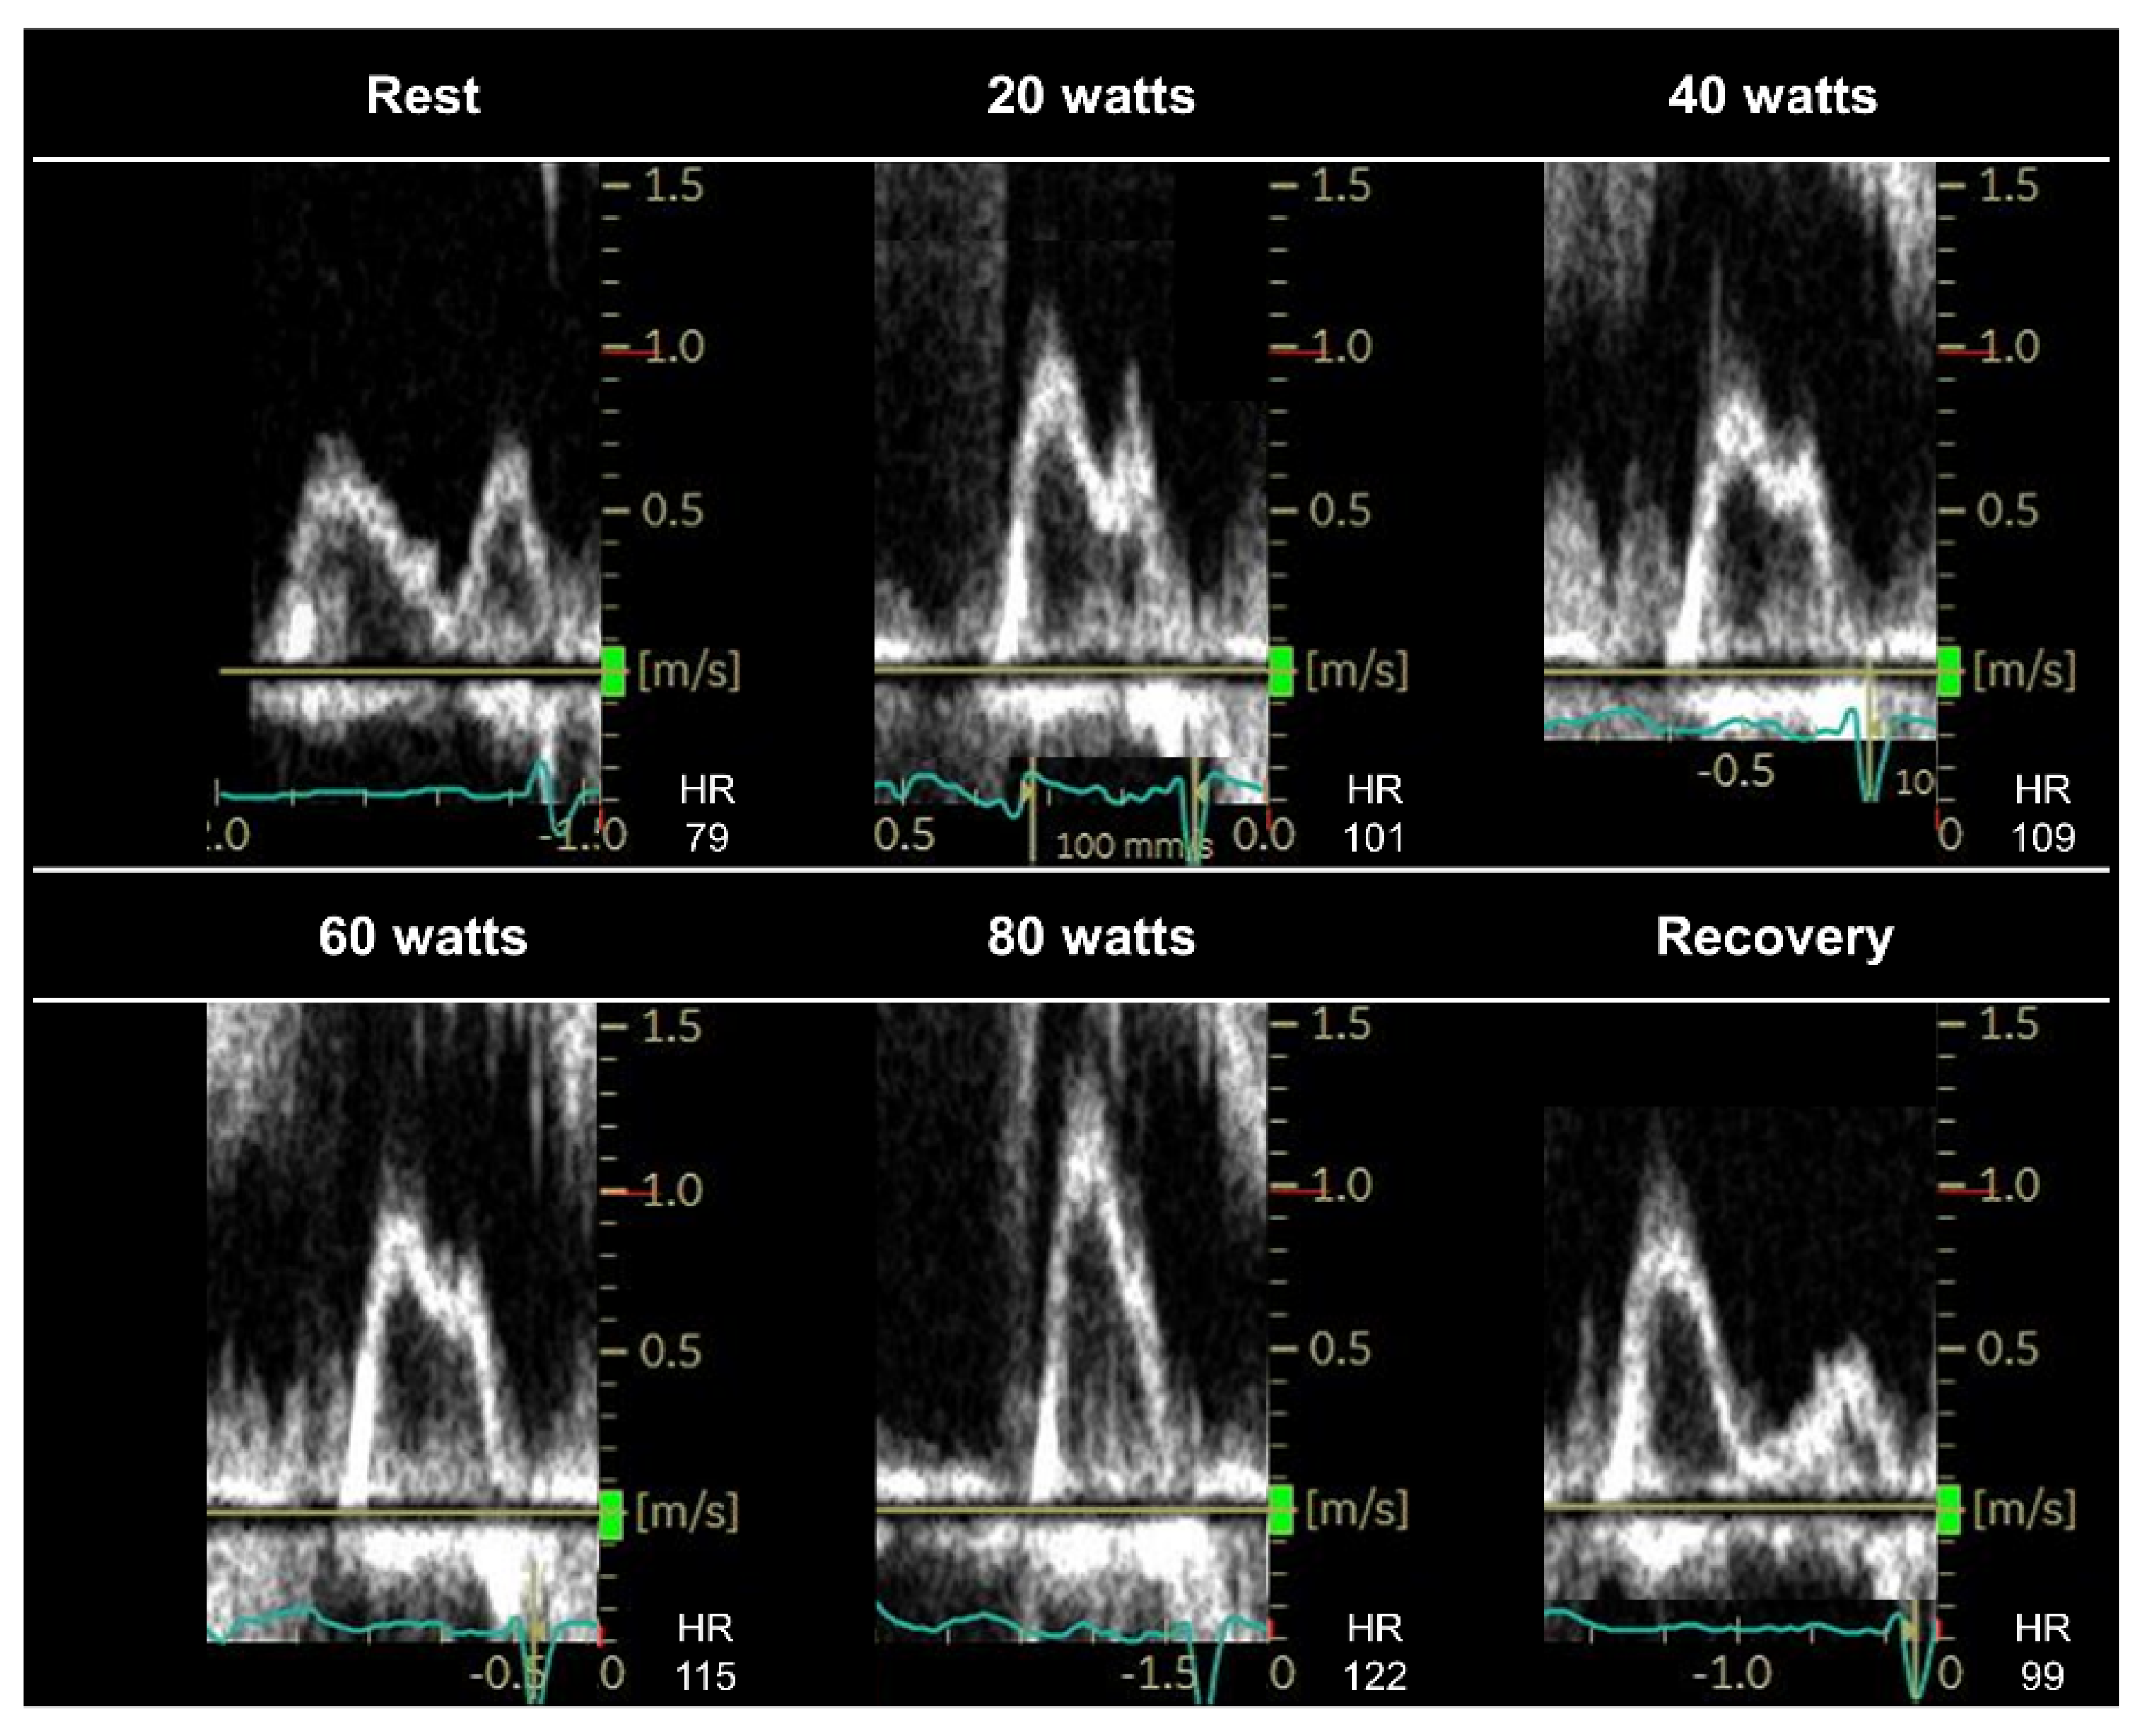

| The E/e′ ratio plays a central role in diastolic stress echocardiography; however, what is the best way to address E–A fusion during exercise? What is the optimal cutoff of E/e′ during exercise in patients with AF? E/e’ ratio cannot be applied to patients with specific diseases, such as mitral valve diseases, mitral valve repair, or prosthetic mitral valves, or in the presence of regional wall motion abnormalities [52]. | The E/e′ ratio during submaximal exercise or the early recovery period can be used to diagnose HFpEF; however, evidence supporting this practice is insufficient. Data on the exercise E/e′ ratio in patients with AF remain limited. Further studies are required to examine the diagnostic value of the exercise E/e′ ratio, using simultaneous invasive right heart catheterization. |